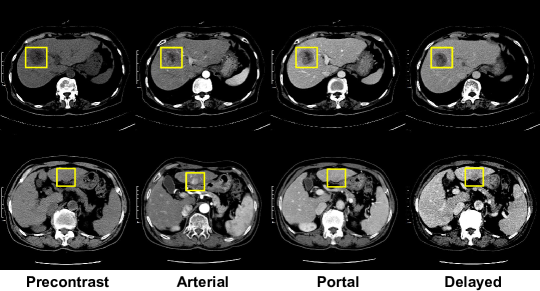

Most publicly available CT datasets contain only the portal phase with per-pixel segmentation labeling [20, 21]. On the contrary, images of multiple phases are required to detect and diagnose the liver lesions. Representatively, HCC warrants diagnostic imaging characteristics of arterial enhancement and portal or delayed washout as stated by major guidelines [5]. Thus, the representational power of deep learning-based models [6, 8, 7] is bounded by the data distribution itself. For example, specific variants of the lesion are difficult to see from the portal phase (Figure 1). Therefore, a variety of hand-engineered data pre-processing techniques are required for deep learning with medical images.

The performance definitively improved when using the multi-phase data. For comparison, the single-phase model received portal phase images copied four times as inputs. The model trained with only the portal phase data obviously underfitted (Figure 3), since several variants of the ground truth lesions are barely visible from the portal CT images.